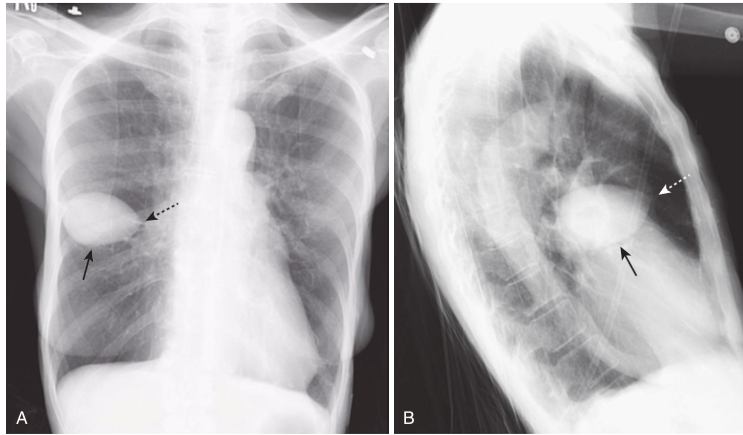

Pseudotumor in the minor fissure.

A, A sharply marginated collection of pleural fluid contained between the layers of the minor fissure produces a characteristic lenticular shape (solid black arrows in images A and B) that frequently has pointed ends on each side, where it insinuates into the fissure so that pseudotumors look like a lemon on frontal (A) or lateral (B) chest radiographs (dotted black arrow in [A] and dotted white arrow in [B]). Pseudotumors always occur along the course of the minor or major fissure, which helps to distinguish them from an actual tumor of the lung.